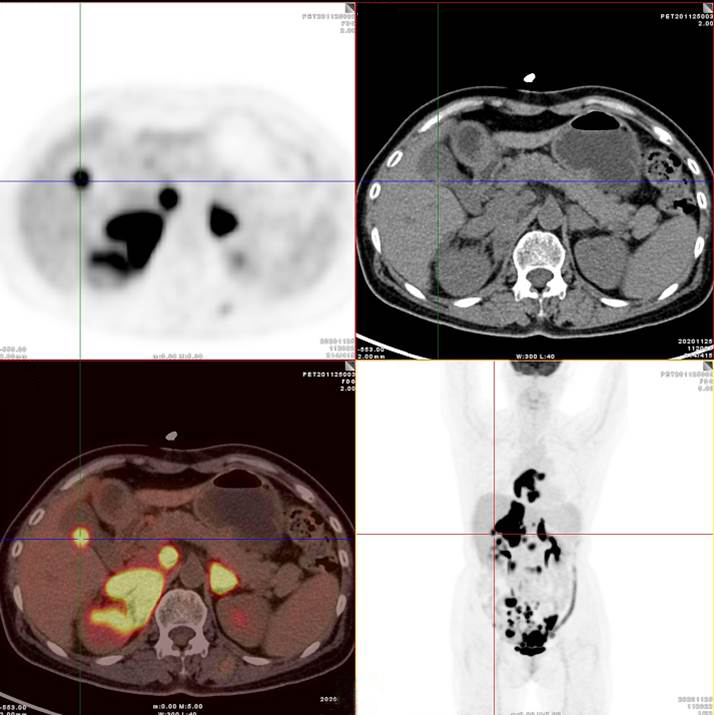

胃、雙腎上腺病灶、腹膜后淋巴結(jié)放射性攝取明顯增高

腸系膜多發(fā)淋巴結(jié)放射性攝取增高

多段小腸腸管放射性攝取增高

影像診斷

考慮淋巴瘤,請結(jié)合臨床病理